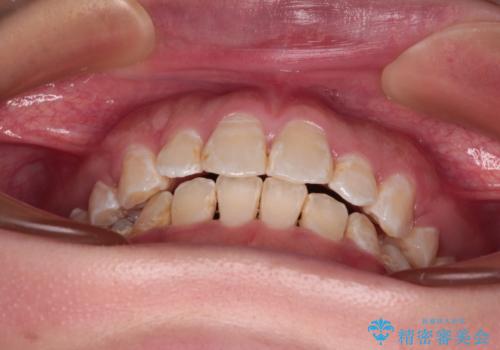

- 前歯のクロスバイトと、口元が閉じにくいとのことで来院された患者様です。

口元の突出感を改善する必要があるため、上下左右の第1小臼歯4本を抜歯し、ワイヤー装置にて矯正治療を行うこととしました。